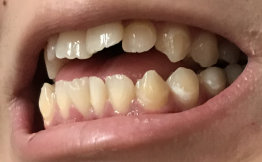

Раньше не обращала внимания, но записала видео крупно, где разговариваю и поняла, что расстояние между челюстями у меня разное. Даже не знаю, как объяснить. Справой стороны, зубы ниже, чем с левой стороны (нижняя челюсть). Особого дискомфорта не доставляет, но смотрится как-то странно, словно челюсть уехала.

Носила брекеты 4 года назад, сейчас стоят ретейнеры, периодически ношу капы. Прикрепляю фото, потому что сложно объяснить ситуацию. Фото сделали полгода назад, чтобы посмотреть на зубы мудрости, тогда не обратила внимания на разницу в расстоянии.

С чем это связано? Стоит ли что-то делать или это не так уж страшно?

Одного снимка недостаточно, чтобы составить дальнейший план действий. Необходим осмотр, оценка прикуса и гипсовых моделей челюстей, фото протокол, изначальная ситуация в полости рта до лечения брекет системой. Проконсультируйтесь очно со стоматологом-ортодонтом.